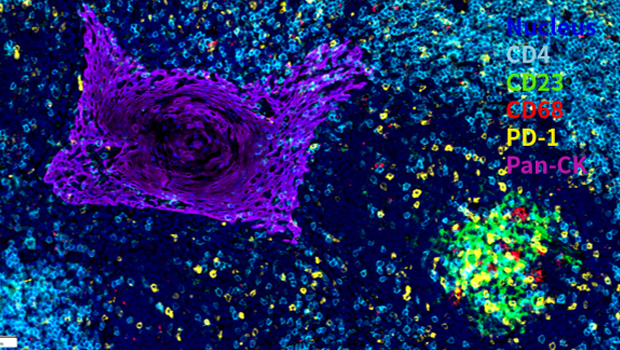

Nucleus,CD4, CD23, CD68, PD-1, Pan-CK